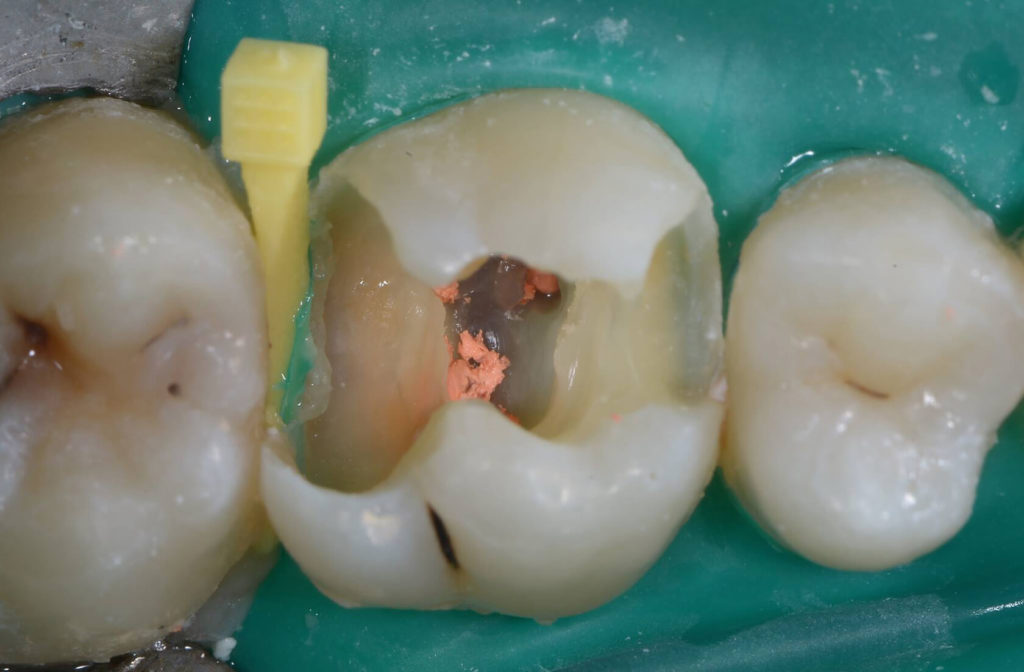

Patient presented with deep distal decay on first molar. Used deep margin elevation and papillectomy. No attempt was made to establish 3 mm biologic width space. Overlay prep and lithium disilicate indirect restoration placed. Photos from 15 month follow up included.